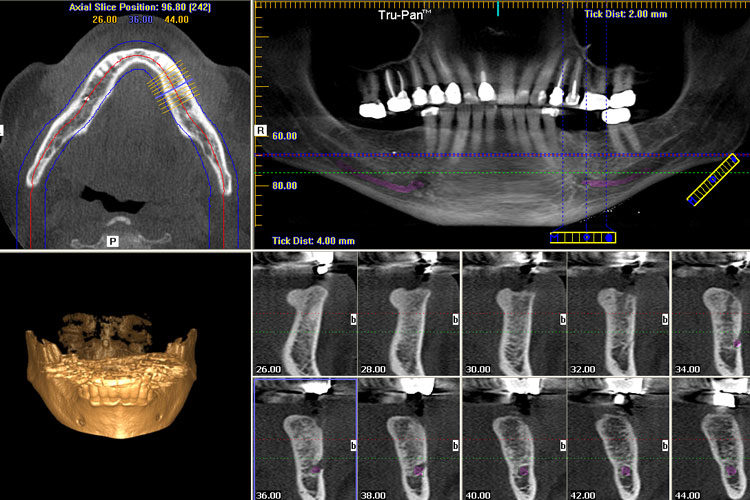

3D CONE BEAM SCANNING

At our office, we are committed to utilizing advanced dental technology to always provide you with the highest level of dental care. We are proud to utilize cone beam 3D imaging technology at our practice. Cone beam 3D technology is an imaging system that provides our dentist and team with a three-dimensional image reconstruction of your teeth, mouth, jaw, neck, ears, nose and throat. We may use dental cone beam 3D imaging to:

Plan dental implant placement

Evaluate the jaws and face

View the head and neck as a comprehensive whole

Diagnose tooth decay (cavities) and other dental problems

Detect endodontic problems and plan root canal therapy

Analyze dental and facial trauma

Plan and evaluate the progress of orthodontic treatment

Visualize abnormal teeth

Cone beam 3D imaging is effective for diagnosing and evaluating dental conditions, as well as planning treatments. One of the advantages of 3D cone beam technology is that it provides our dentist and team with a view of your mouth and supporting structures that is more comprehensive than that provided by digital X-rays.